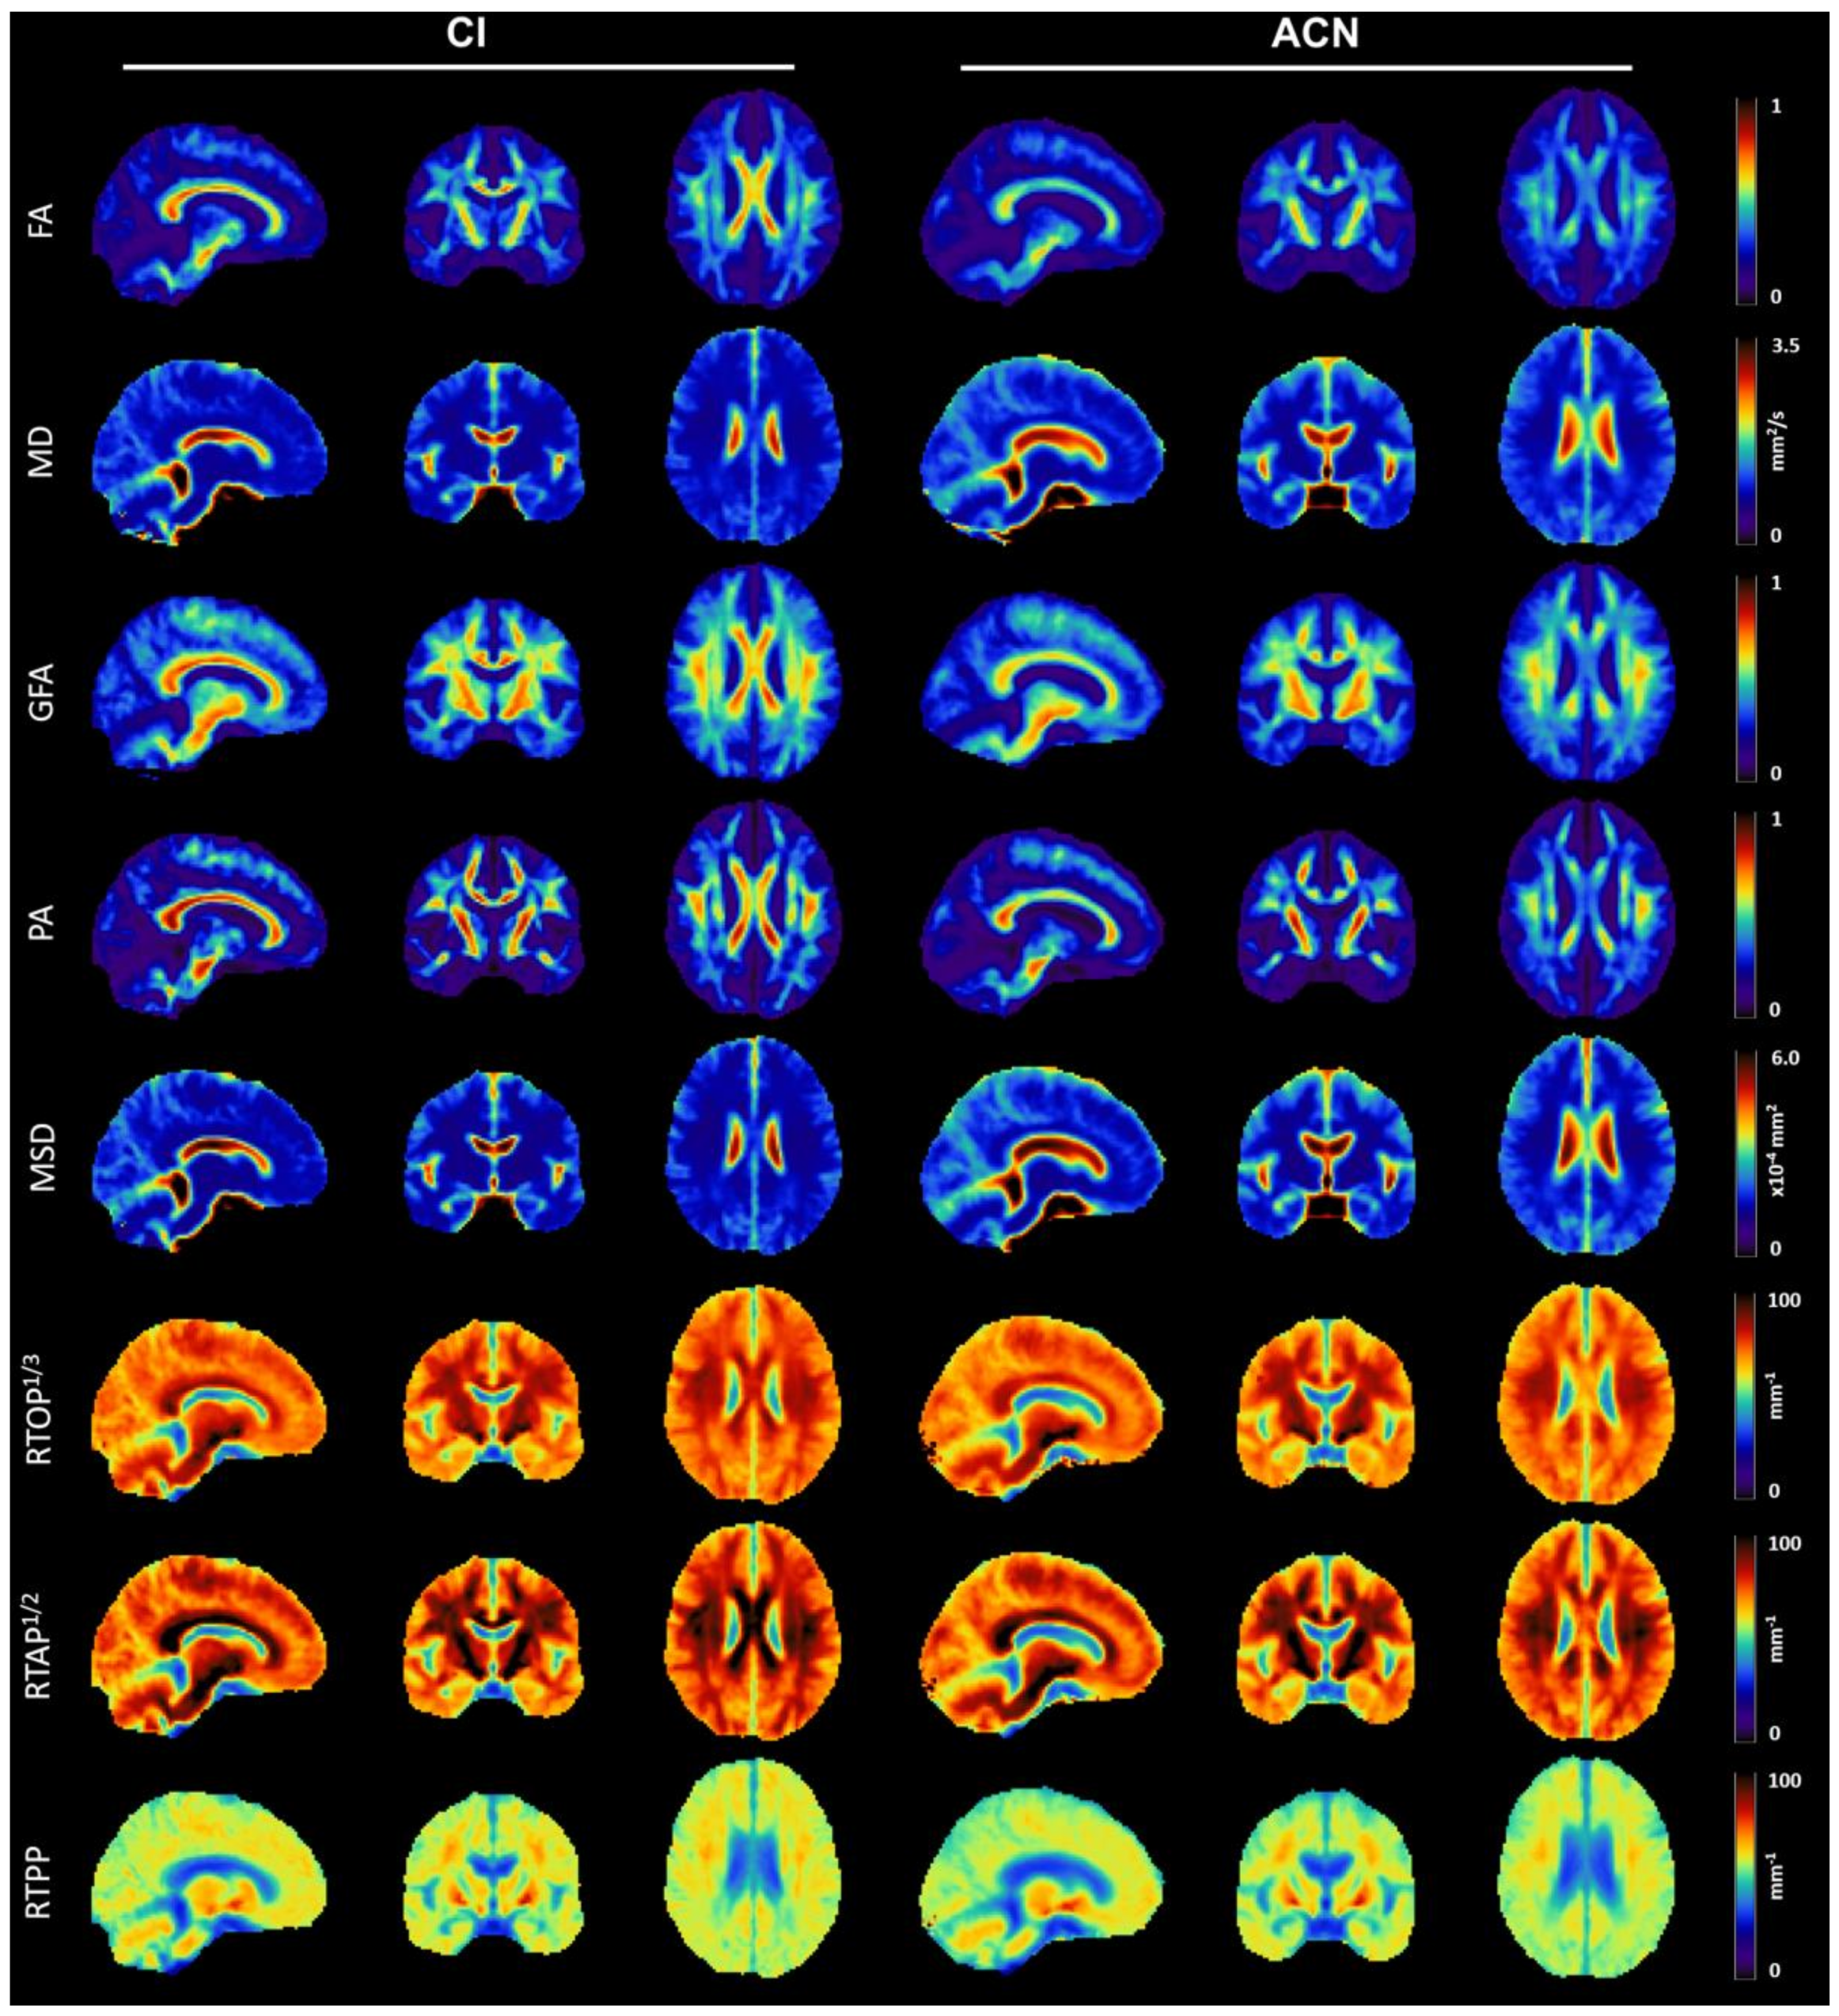

3.2. Qualitative Analysis of Microstructural Indices

3.3. Statistical Analysis of MRI-Derived Numerical Biomarkers